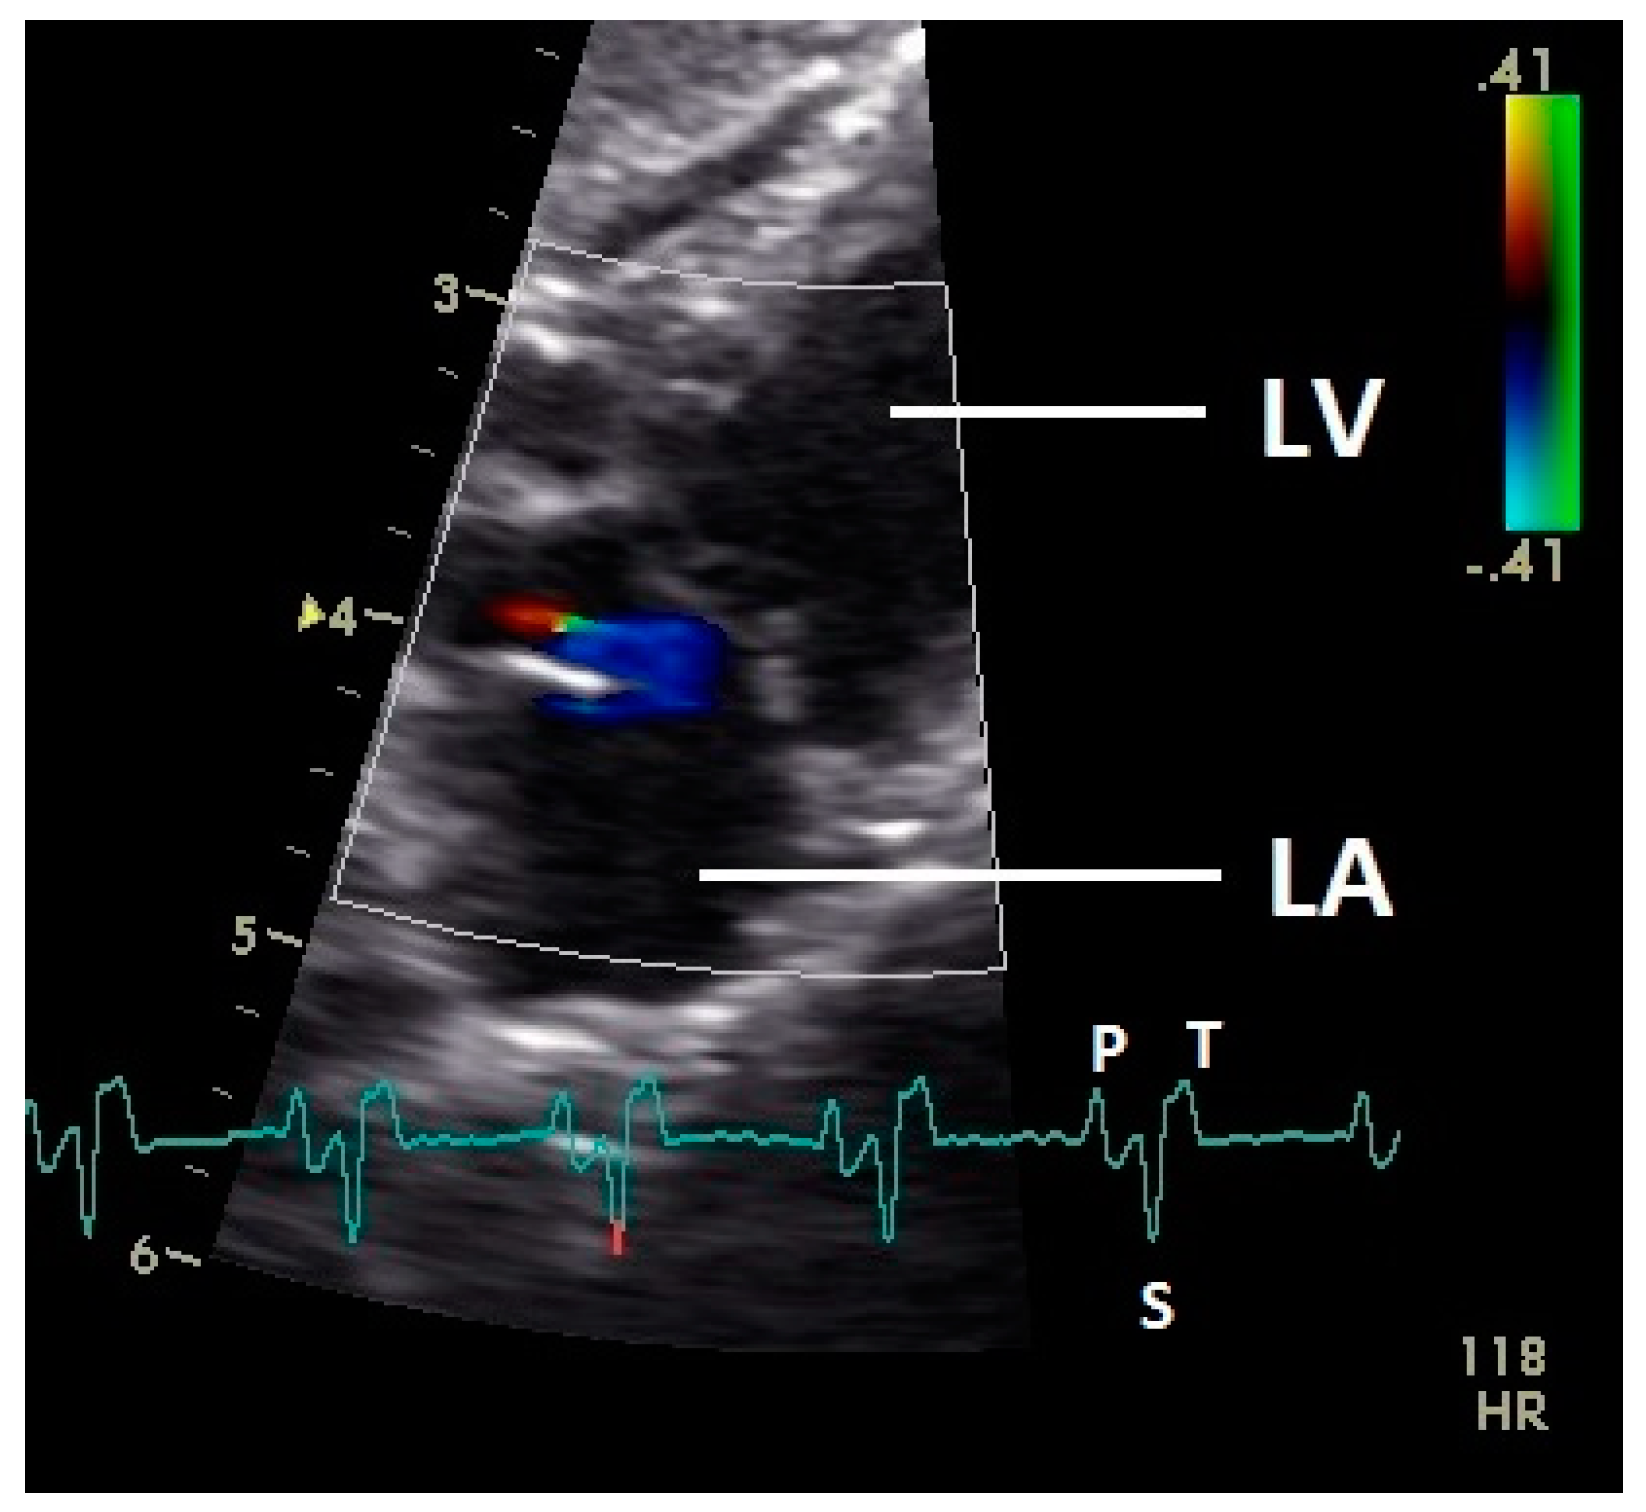

After the P wave of the ECG in the phase of the relaxation of myocardium of the left atrium, a little blue filling signal over the AV valve was seen in the some pigeons (n = 27; 62.8%) with the used settings (Figure 5). In all pigeons a later and faster blue inflow signal in the atrium in the time of the descending part of the T wave was recorded over the AV valve to the left part of the atrium (significant difference Chi-squared test p ≤ 0.001). At the same time a red signal was seen right and left from the valva pulmonis in some pigeons (25 out of 43 birds; 58.1%; Figure 6). The position of the valva pulmonis was almost constant in diastole (Figure 7) and systole (Figure 5 and Figure 6).

Figure 5.

Color Doppler image of the early blood inflow in the left atrium (red and blue signal). LV: left ventricle; LA: left atrium; HR: heart rate. Electrocardiogram: P: P wave, S: S wave, T: T wave. The color scale on the right of the image is calibrated in m s−1.